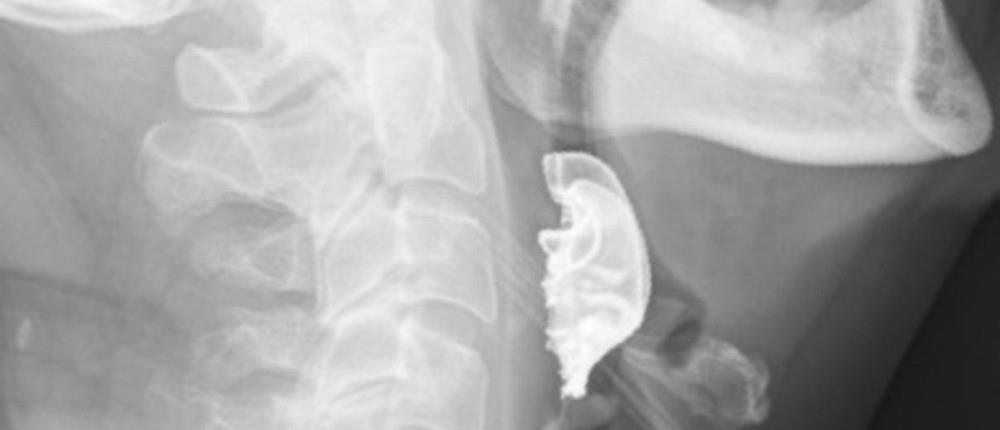

Τελικά, μέσω μιας διαγνωστικής διαδικασίας οι γιατροί εντόπισαν το ημικυκλικό αντικείμενο σφηνωμένο πάνω στις φωνητικές χορδές του άνδρα, που είχε προκαλέσει εσωτερικές φουσκάλες και πρήξιμο.

Ο 72χρονος, που είχε χάσει την μασέλα του κατά την πρώτη του επίσκεψη στο νοσοκομείο αλλά δεν είχε φανταστεί ότι αυτή βρισκόταν στον... λαιμό του, εισήχθη εσπευσμένα στο χειρουργείο για την αφαίρεση της μερικής οδοντοστοιχίας, που αποτελούνταν από το μεταλλικό πλαίσιο που εφαρμόζει στην οροφή του στόματος και τρία τεχνητά δόντια.